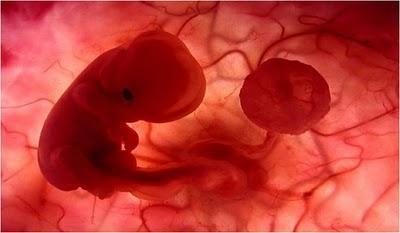

UN EMBRIÓN DE POCAS SEMANAS QUE SE ENCUENTRA EN EL INTERIOR DEL ÚTERO DE SU MADRE.

ESTÁ EN EL INICIO DE SU DESARROLLO.

ES APENAS EL PRINCIPIO DE UN SER HUMANO Y EN ESTE ESTADO PODRÍA SER CONFUNDIDO CON EL EMBRIÓN DE UN MACACO.

JUNTO A ÉL SE ENCUENTRA EL SACO VITELINO,PROPORCIONÁNDOLE LOS NUTRIENTES QUE NECESITAEN LAS PRIMERAS SEMANAS DE VIDA.

ALREDEDOR DE LA 8ª SEMANA DE GESTACIÓN EL SACO VITELINO PIERDE SUS FUNCIONES. EL CORDÓN UMBILICAL EMPEZARÁ AALIMENTARLO CON NUTRIENTES TOMADOS DELCUERPO MATERNO A TRAVÉS DE LA PLACENTA.

MIENTRAS TODO ESTO SUCEDE, ÉL FLOTA TRANQUILAMENTE,EN EL ÚTERO DE SU MADRE.